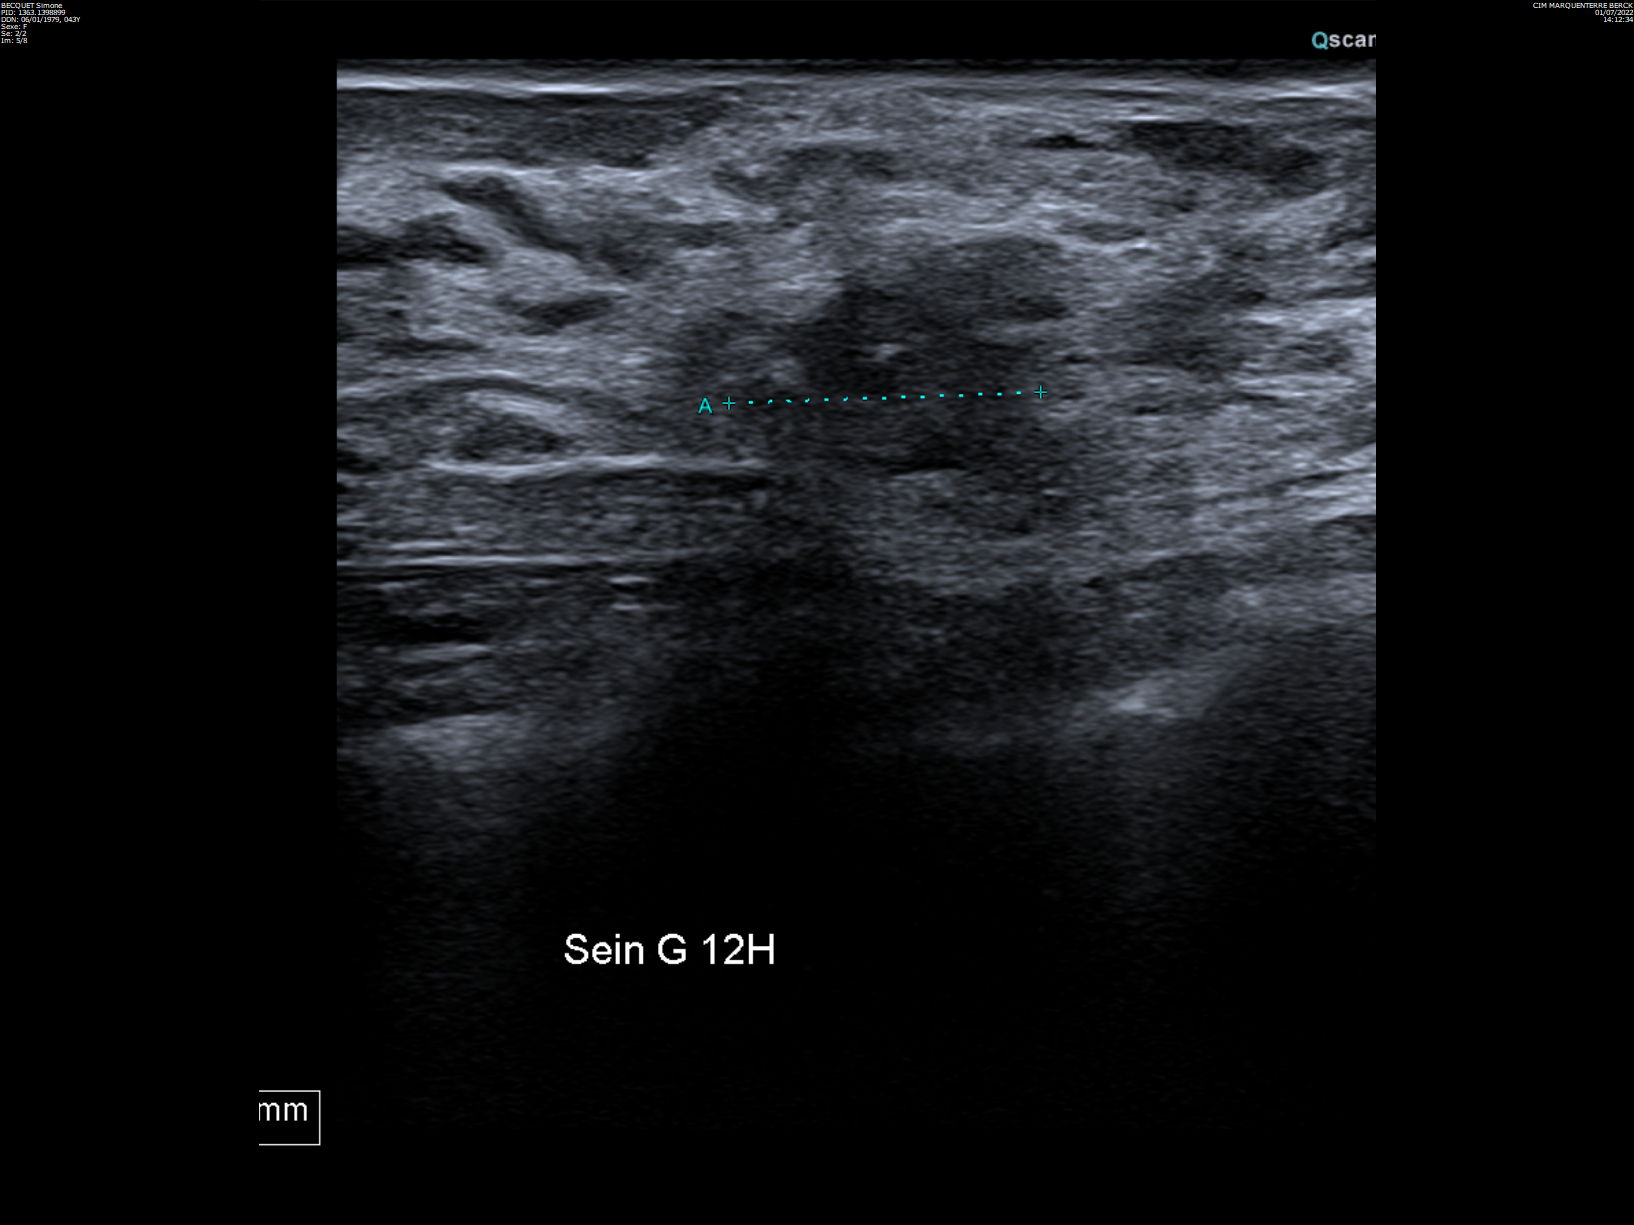

43-year-old woman, palpation of left breast nodule.

MammoScreen® points to a left nipple retro opacity associated with to cluster of micro calcifications scored at a 9.

Breast biopsy confirms an infiltrating adenocarcinoma SBR 2, RH+ HER2-, Ki67 at 15%.